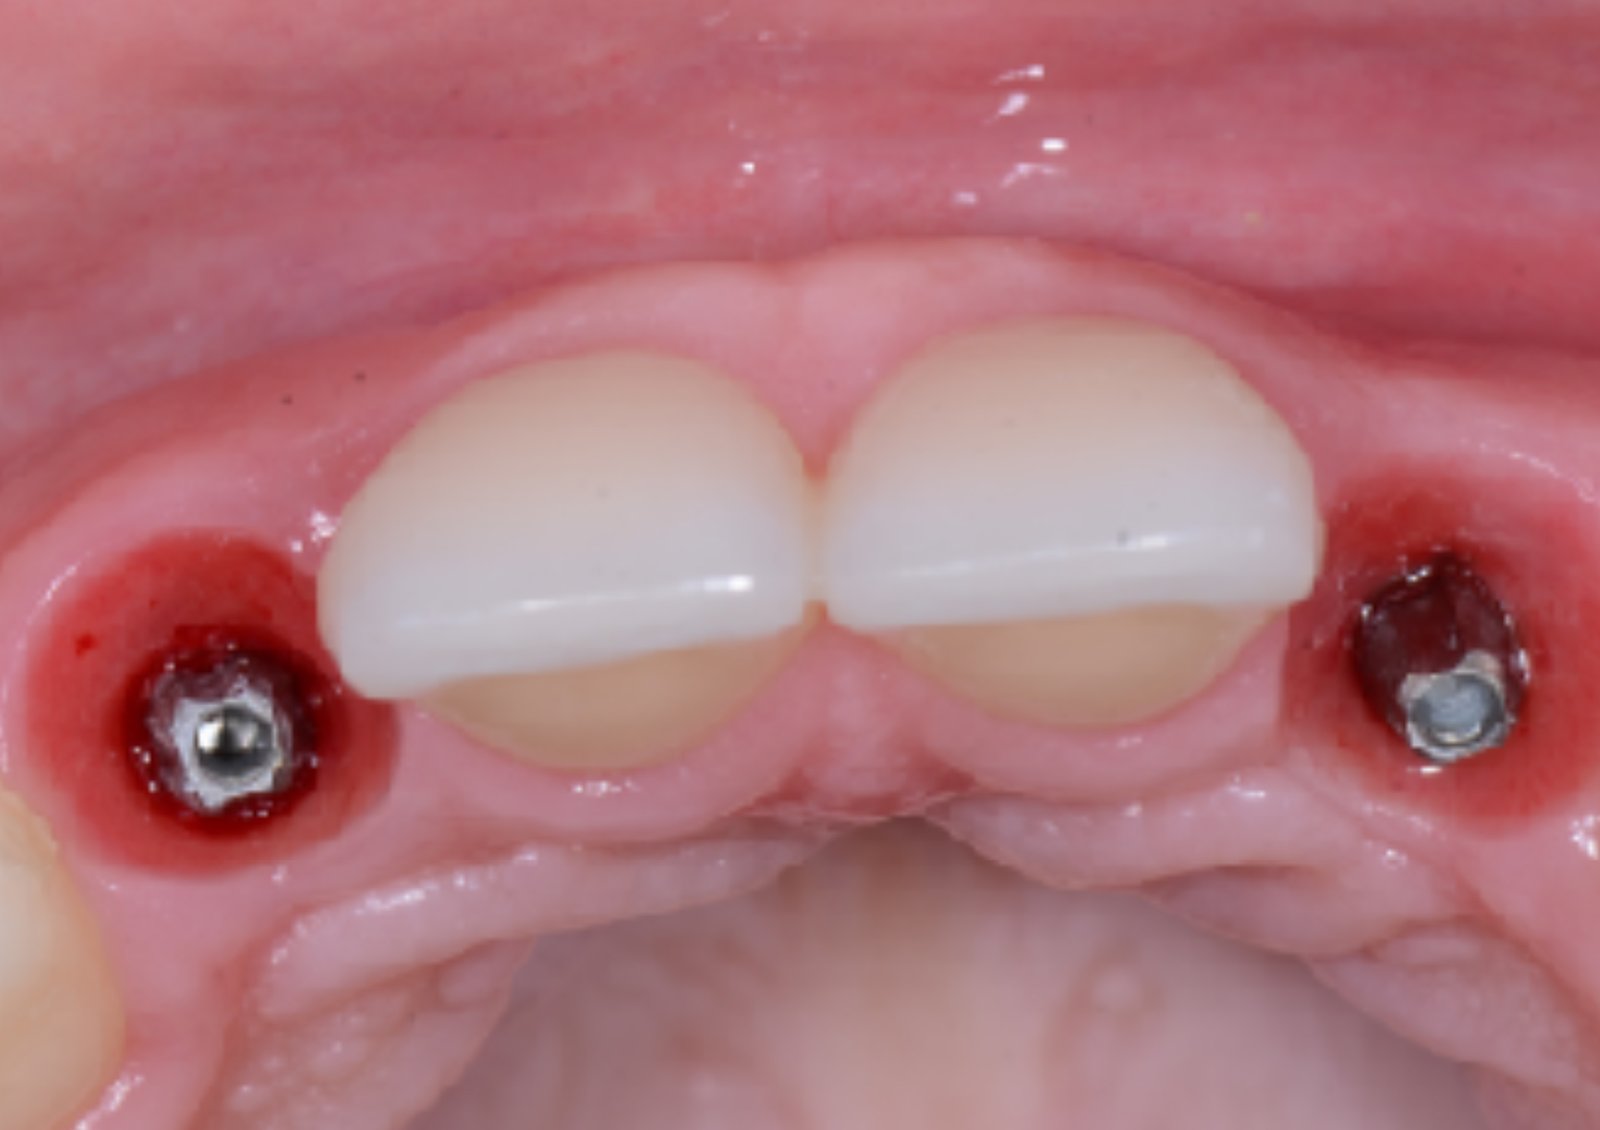

foi realizado a exposição do leito regenerado,

instalação de implantes Implacil Slim 2.5 x 13mm, associado a enxerto de tecido conjuntivo para aumento dos tecidos moles na zona de transição no sulco perimplantar.